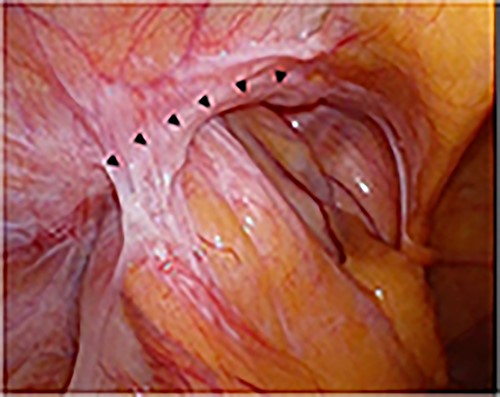

Intraoperative findings of the left inguinal region after peritoneal incision; the black triangles indicate the hernial orifice; the dotted circle indicates the assumed hernia sac; the black cross indicates the internal inguinal ring.

A laparoscope was inserted through a 12-mm umbilical port. In the laparoscopic view, on the left side, the sigmoid colon had retracted into the hernia lateral to the left epigastric artery, suggesting a sliding hernia of the sigmoid colon (Fig. 6). The size of the hernial orifice was ~30 mm. On the right side, the direct inguinal hernia was 20 mm in size. Accordingly, 12-mm ports were created at the level of the umbilicus aligning with the left and right mid-clavicle. The left side had been repaired first. After peritoneal incision and preperitoneal space dissection, the inner inguinal ring was found to be too small relative to the physical findings. Instead, the hernial orifice was observed under the conjoint tendon toward the ventral dorsal direction (Fig. 7). Based on the aforementioned findings, the left interparietal inguinal hernia was reconfirmed. Subsequently, preperitoneal repair of the hernia was performed with a mesh using the same surgical procedure as that for a standard TAPP repair. The hernia was repaired in the same way on the right and left sides. On postoperative Day 1, the patient resumed oral intake. Further, on postoperative Day 2, he was discharged uneventfully.